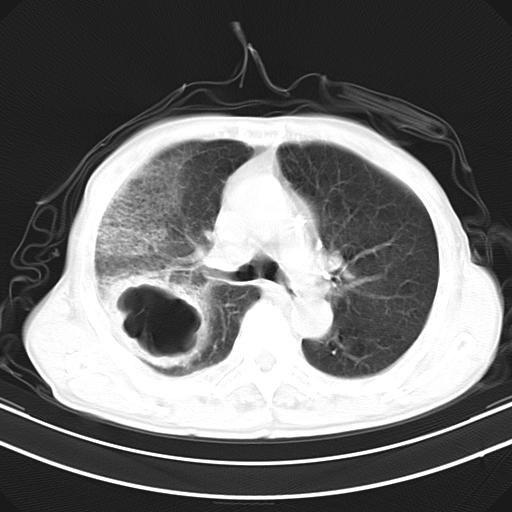

抗炎治疗10天后复查

抗炎治疗10天后复查:右上肺模糊阴影明显减少。